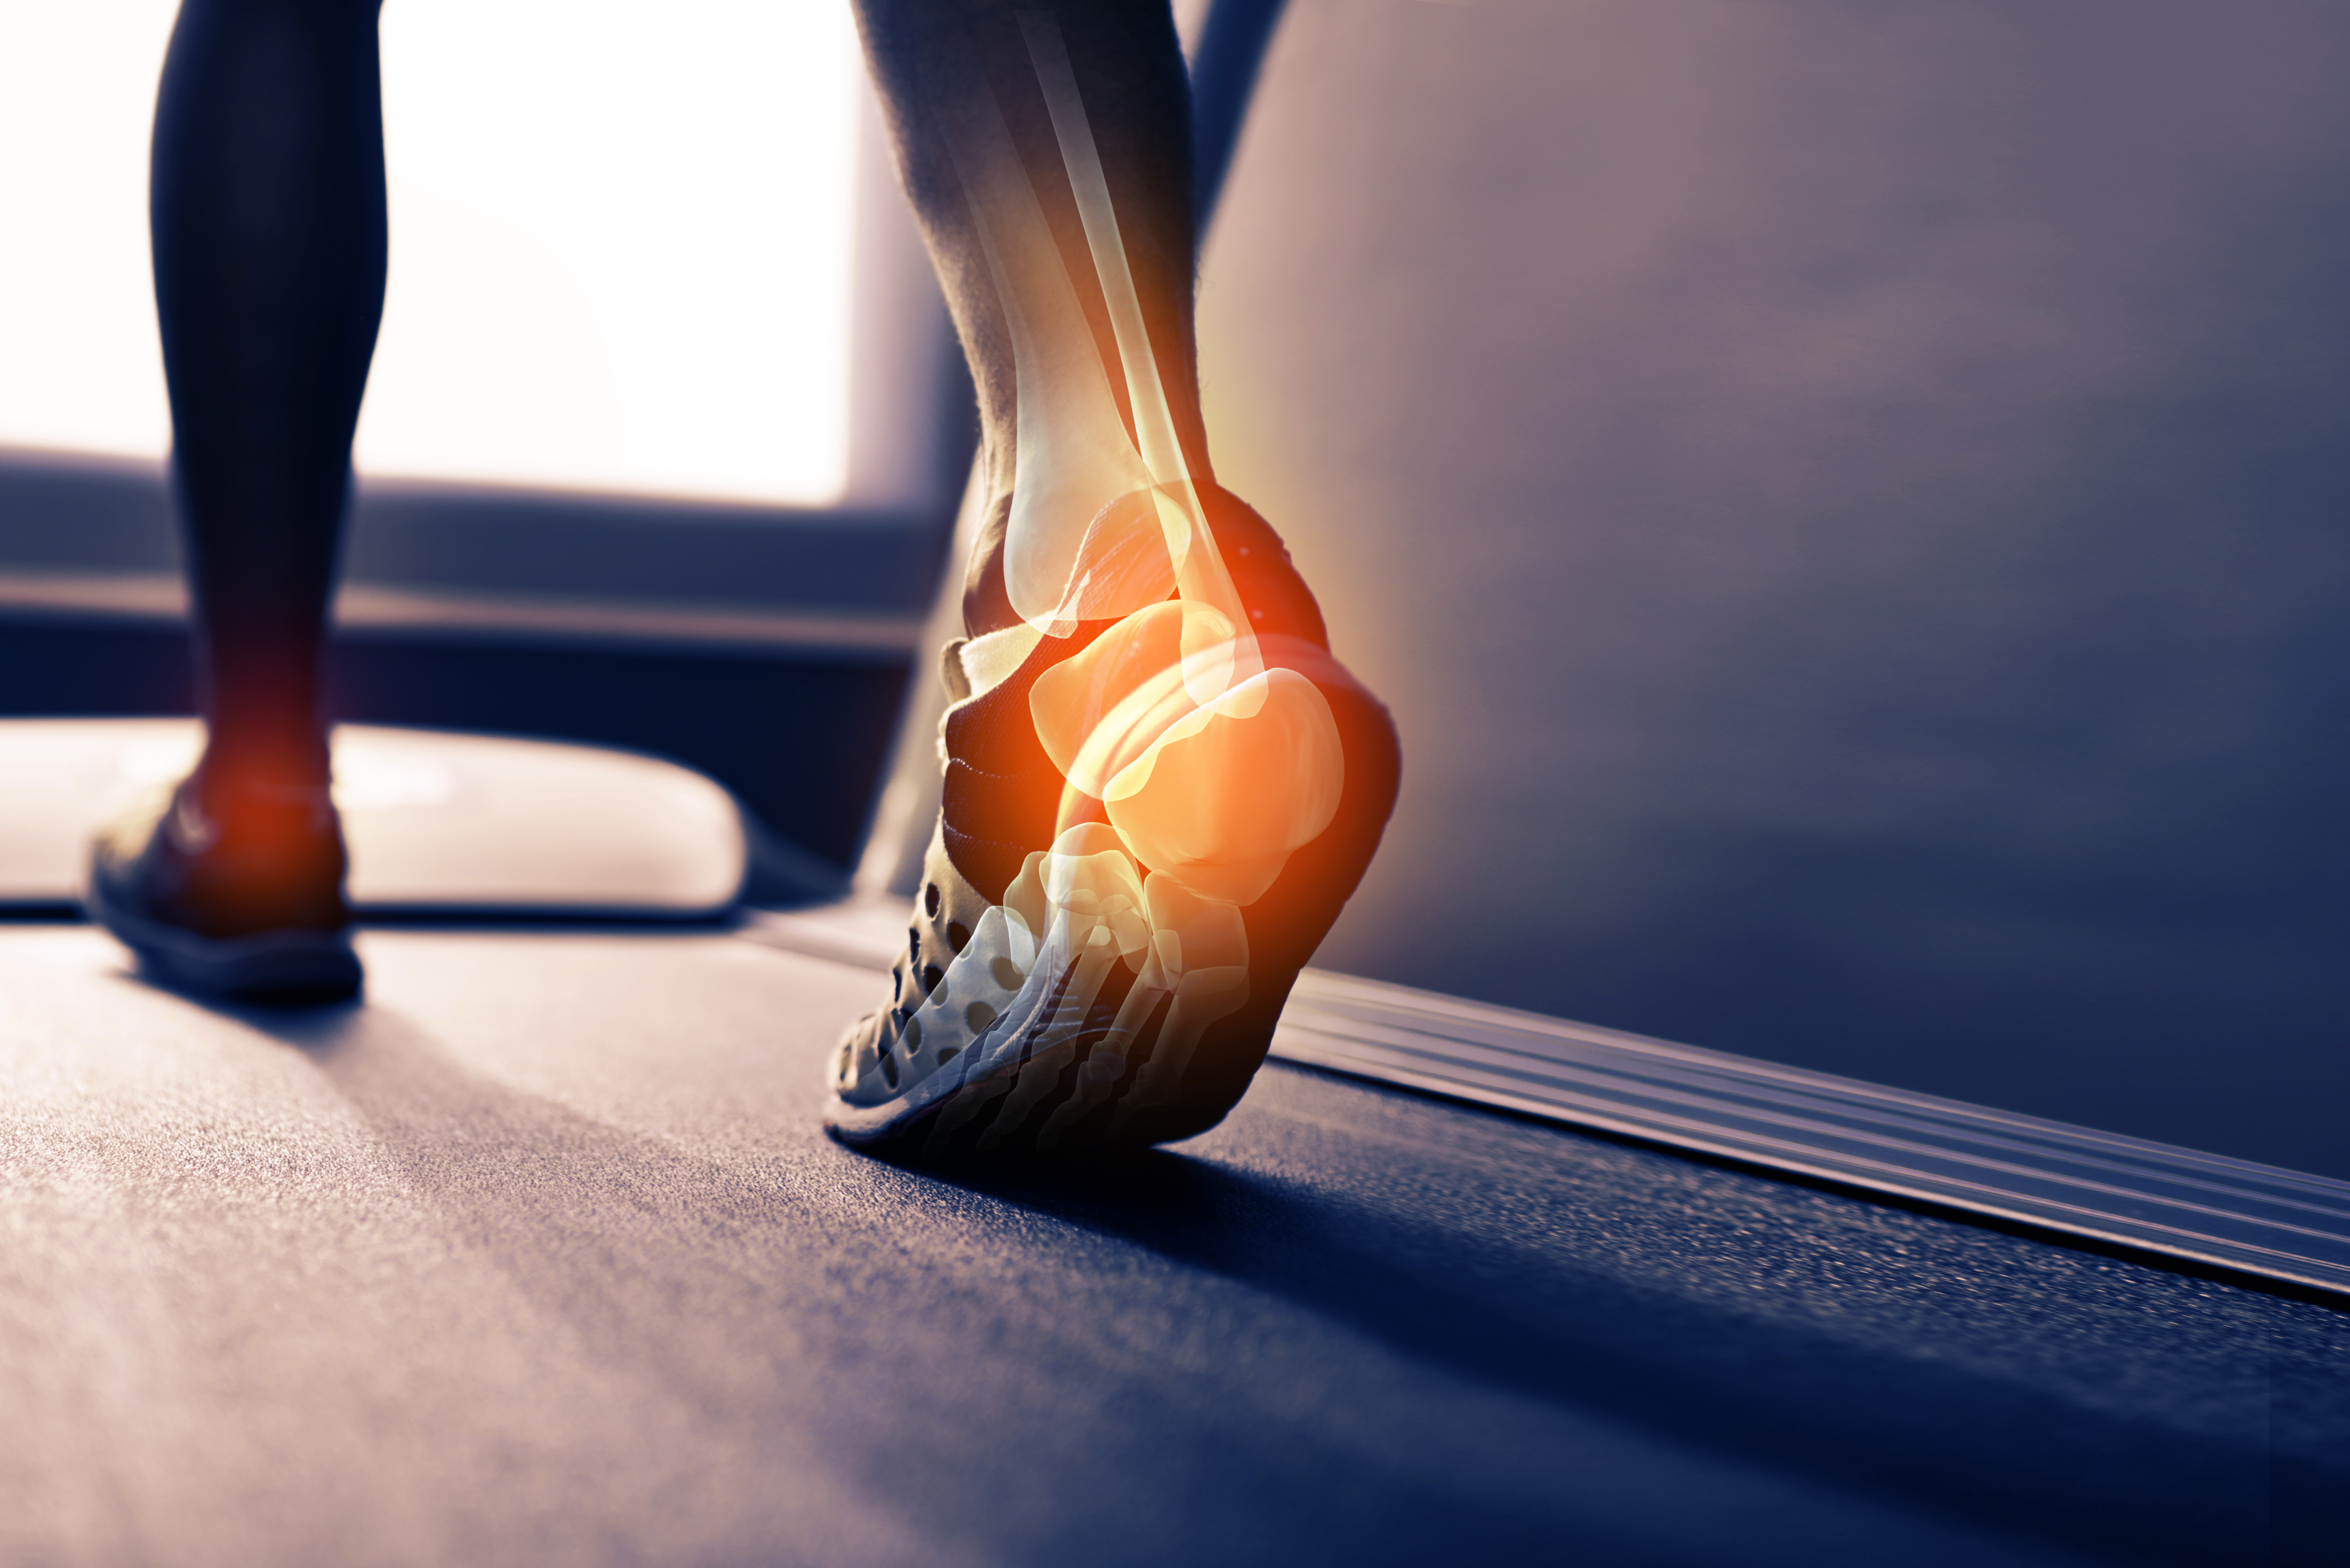

Treatment for top broken heel

- treatment for broken heel